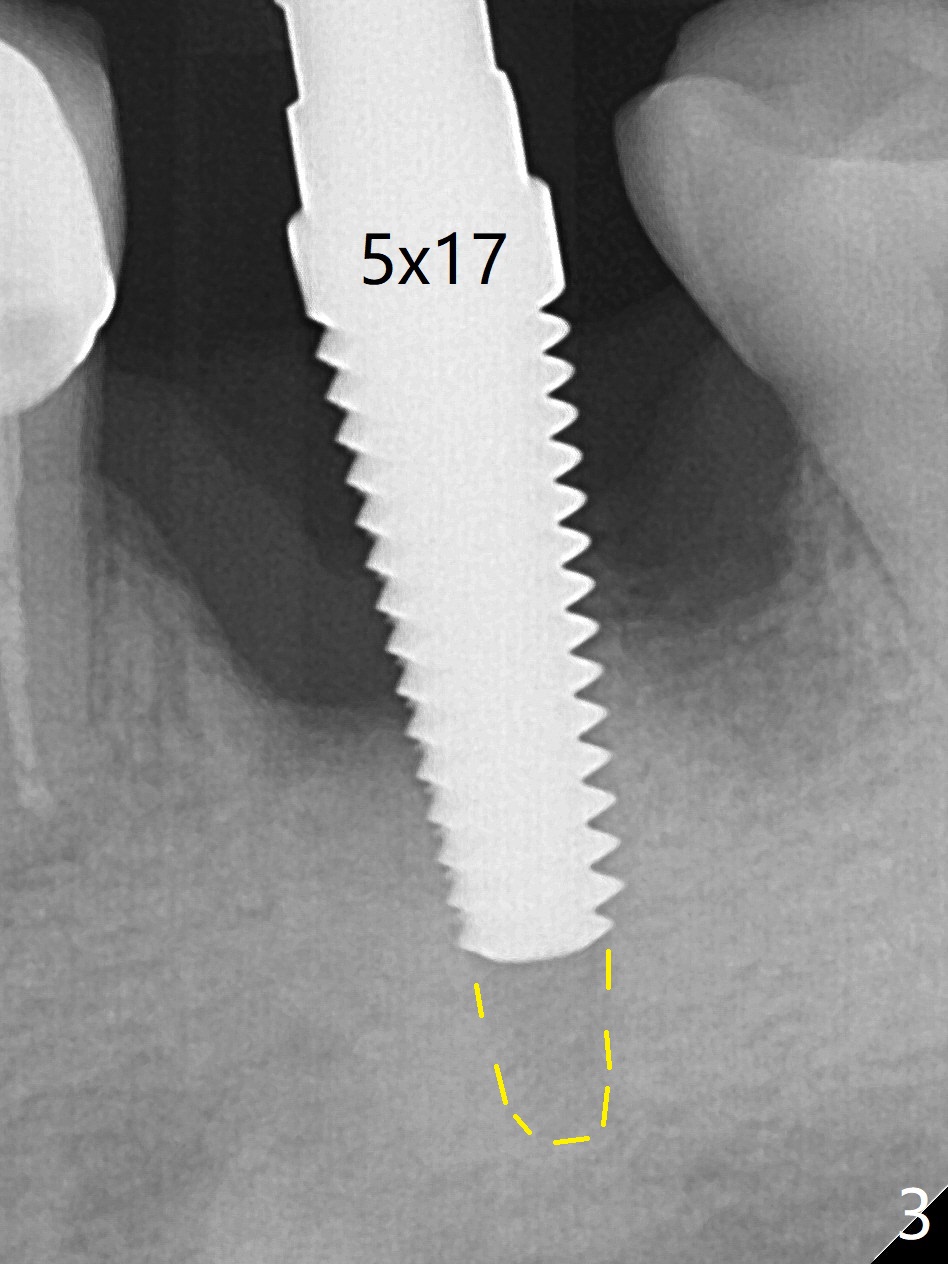

After extraction of the tooth #19 with mesial root fracture (Fig.1 ^) and curettage, the initial osteotomy in the septum is found to need to be distalized (Fig.2 arrow). Following sequential osteotomy, a 5x17 mm tap cannot reach the expected depth (Fig.3 yellow dashed line) because of the dense bone. A shorter implant is placed with >60 Ncm (Fig.4). An immediate provisional is fabricated after placement of a 4.5x5 mm abutment and Vanilla/Osteogen graft (Fig.5 *). The mesial and distal sockets heal 4 months postop (Fig.6). The bone density in the mesial and distal sockets continues to increase when a crown is cemented (~4.5 months postop, Fig.7). The implant at #19 was placed in the middle of the bone (Fig.8).